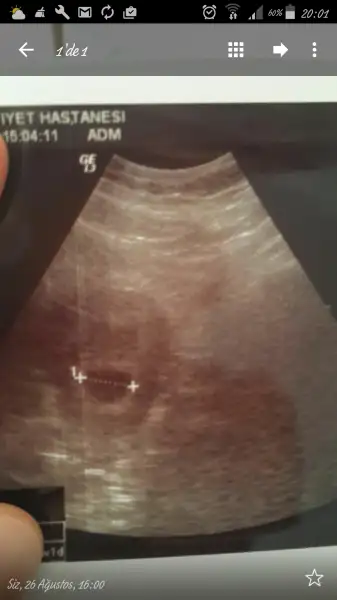

Bebeğim 7+5 haftalık bugün kalp atışlarını duyduk çok şükür

Karından usg yorununuzu merak ediyorum

Usg karındansa kız gibi,vajinalsa erkek gibi